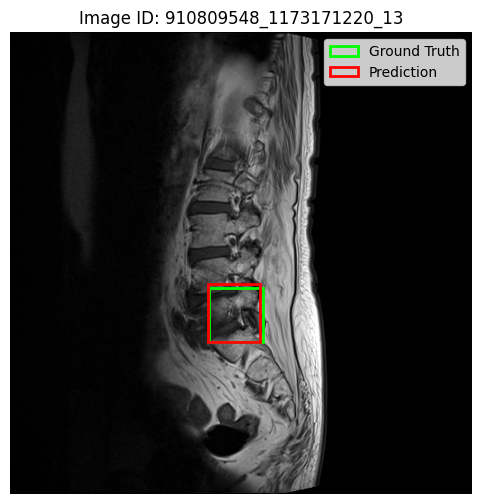

Prior to classification, we trained a 25-class Faster R-CNN model to localise spinal conditions at specific vertebral levels. Figure 6 presents qualitative results on three representative cases, showing predicted bounding boxes (red) and ground truth annotations (green). In the first two examples, the predicted bounding boxes are well-aligned with the ground truth, capturing the target regions with high spatial fidelity. The third image, however, reveals less overlapping predictions, reflecting reduced precision. These visualisations illustrate both the strengths and limitations of the detection module in complex anatomical contexts.